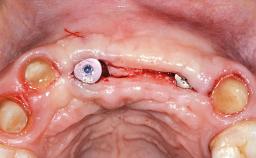

Replacement of Six Teeth with a Fixed Dental Prosthesis on Four Bone-Level Implants

In November 2010, a 44-year-old woman presented to the Harvard School of Dental Medicine seeking options to replace her failing six-unit conventional prosthesis. Having served for approximately 10 years, the fixed partial denture had repeatedly needed recementation after chronic dislodgement over the past few months. Following these episodes, the patient requested further evaluation of her current prosthesis and showed interest in exploring other options for a fixed solution. The patient was in good overall health, presenting with no systemic contraindications to implant therapy or any history of allergies; she did not smoke and was on no medications. Being a well-motivated individual, she regularly saw her general dental practitioner and effectively complied with oral hygiene requirements.